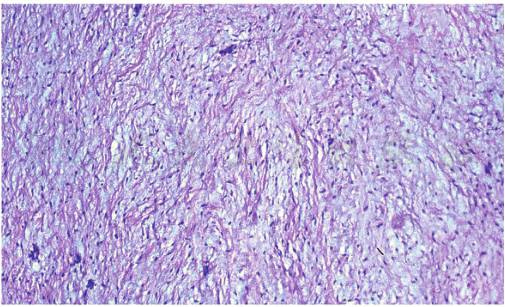

肉眼观肿瘤边界不清,剖面为灰白色,半透明,质脆,富有黏液,常无包膜。镜下见瘤细胞呈梭形或星形,排列疏松,核卵圆形,染色深,偶见不典型核,大小形态不一,但核分裂罕见。瘤细胞间有大量淡蓝色黏液基质,肿瘤有时生长加快,可能是黏液基质堆积的结果。肿瘤内有时见有少量散在的牙源性上皮剩余(图1)。肿瘤内纤维成分多者,又称为纤维黏液瘤。

图1牙源性黏液瘤

瘤细胞呈梭形或星形,排列疏松,瘤细胞间有大量淡蓝色黏液基质